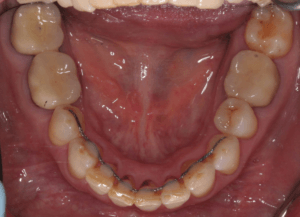

Для предварительной подготовки были привлечены пародонтолог и ортопед, поскольку отсутствие нескольких зубов, заболевание пародонта и дефекты твердых тканей зубов сопутствовали основной патологии. Проведены пародонтологические процедуры, вылечен кариес и его осложнения, изготовлены временные коронки для зубов с большим разрушением. На фото — временные коронки на боковых зубах.

Искривление окклюзионной кривой (плоскости смыкания зубов), возникшее в результате парадонтита, успешно удалось устранить, используя накусочные брекеты на верхних резцах и микроимплант, установленный во фронтальном участке нижней челюсти: